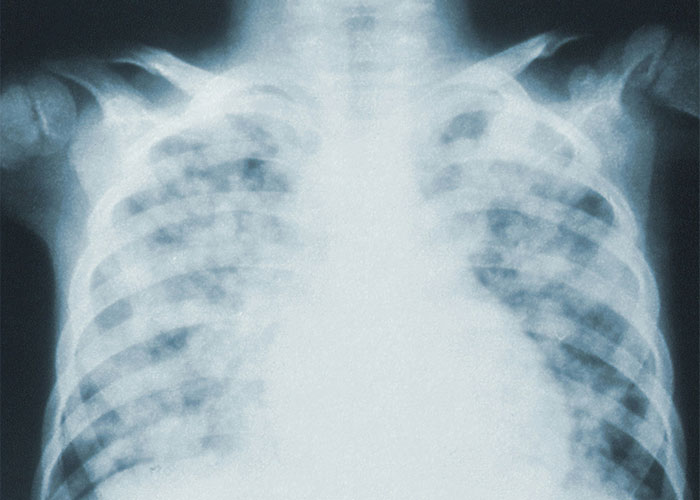

#8

Pneumothorax (collapsed lung) can just like...happen. if you sneeze or cough or just breathe wrong, your lung can"nope" and collapse.

Image credits: cat_prophecy

#30

Humans can live with one lung, the remaining one will expand and partially fill the rest of the chest cavity, which can lead to cardiac distress. It's not the most pleasant existence, but people have made it up to 30 years like that.

Image credits: mck1llguddy